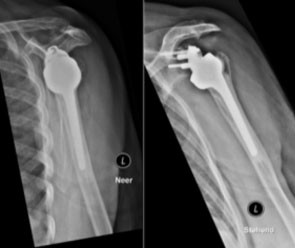

Etwas anders verhält sich die endoprothetische Versorgung bei Arthrose und gleichzeitig bestehendem schwerem Sehnenschaden (Cuff-Arthropathie). Je nach Ausmass der Schädigung der Rotatorenmanschette muss ein spezieller Prothesentyp zur Anwendung kommen. Es handelt sich hier um die sogenannte Inverse (umgekehrte) Endoprothese. Dabei wird, anders als bei den bereits beschriebenen Prothesentypen, der Oberarmkopf zur Pfanne und die Schulterpfanne zum Kopf.

Zum Einen gewährleistet dieser Prothesentyp bei fehlender Rotatorenmanschettenfunktion eine Primärstabilität, zum Anderen wird das Rotationszentrum verschoben, was mit günstigeren Hebelverhältnissen einhergeht. Die Beweglichkeit bei der inversen Prothese ist somit nicht mehr auf die intakte Rotatorenmanschette angewiesen, sondern wird durch den darüber liegenden Deltamuskel ausgeführt.

Die Inverse Endoprothese der Schulter kommt meist bei Patienten über 65 Jahren zum Einsatz. Voraussetzung ist ein intakter Deltamuskel und eine ausreichende Knochensubstanz, damit die stabile Verankerung der Prothesenanteile gewährleistet ist.

Beispiel einer inversen Schulterprothese (Affinis invers,Mathys, Enovis)

Postoperatives Röntgenbild einer inversen Schulterprothese